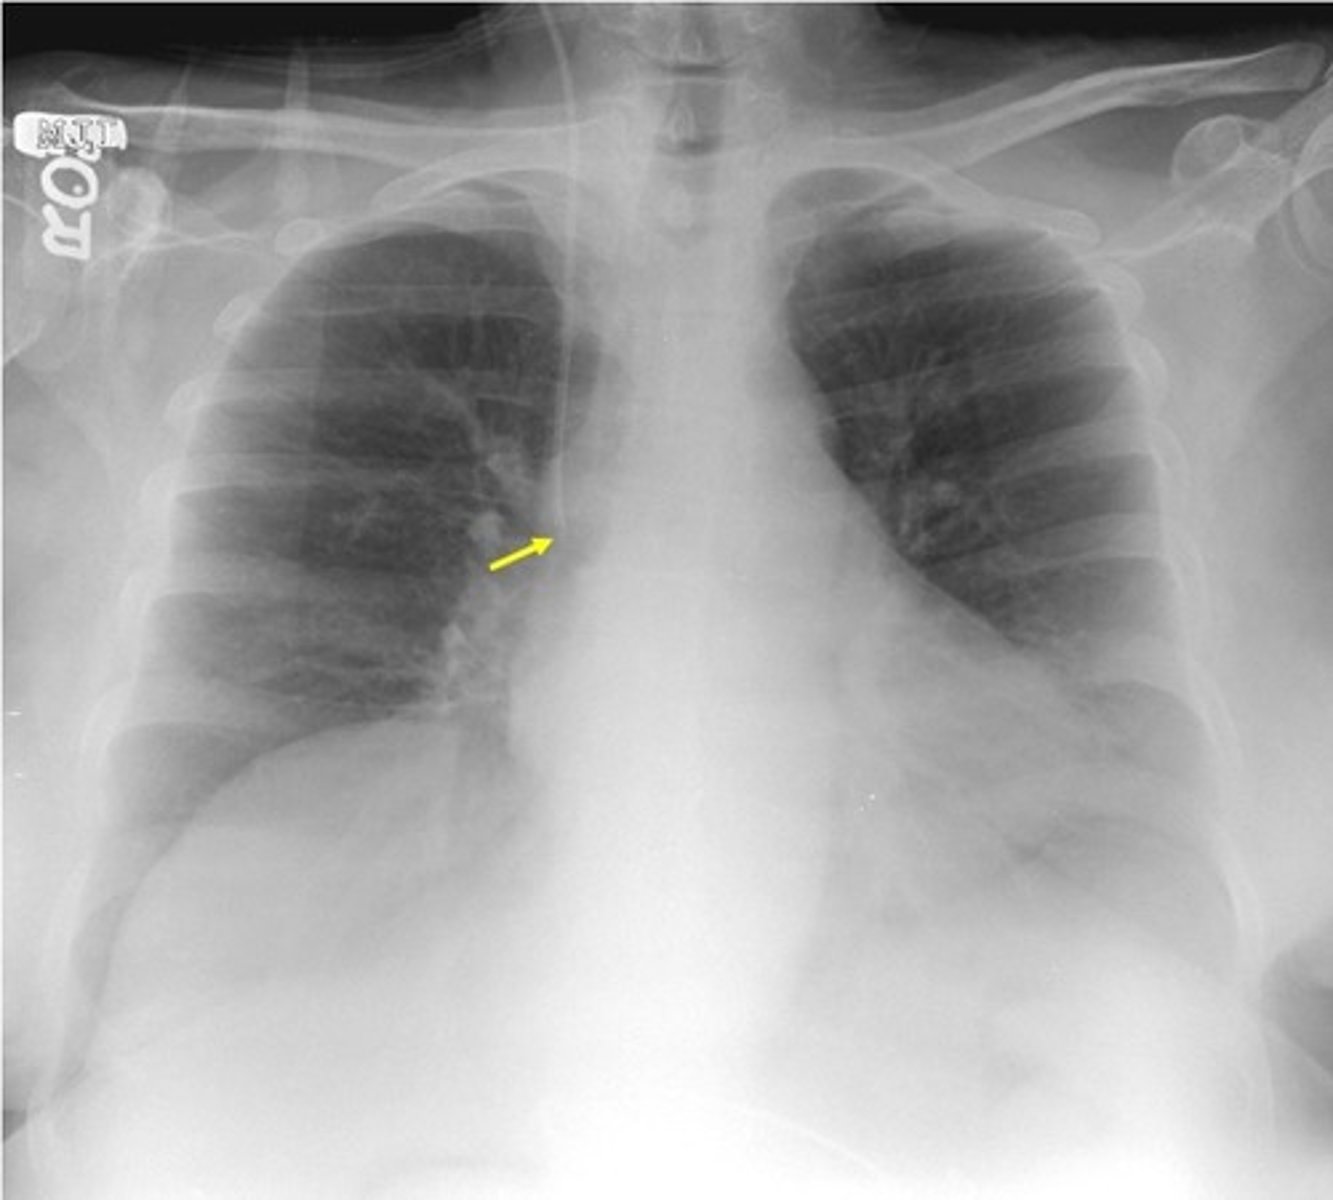

Pneumococcal Pneumonia appearance

-obscured the left heart border and diaphragm

Lingular pneumonia appearance

-hazzy (whiteness) over the effected area

(PICTURE ON LEFT)

Pulmonary edema appearance